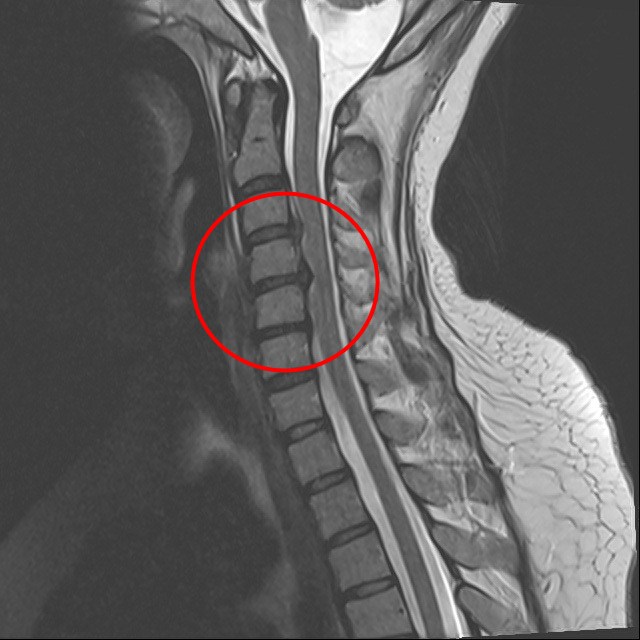

楊小姐的頸椎第三節到第五節間的椎間盤軟骨已經破裂,壓迫到脊椎神經。

因為楊小姐的頸椎第三節到第五節間的椎間盤軟骨破裂,已經壓迫到脊椎神經,引起交感神經症狀,導致她只要一躺平,胸悶、胸痛的症狀就更嚴重。為了改善她的症狀,我使用頸椎微創手術「頸椎間盤切除及融合手術」移除破裂的兩塊椎間盤,再使用融合器,穩定頸椎讓骨頭得以生長。